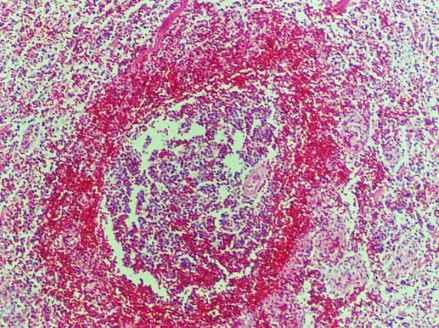

链球菌常根据其在血琼脂培养基上溶血环的大小,分为甲、乙、丙三型。 其中乙型溶血性链球菌具有完全的溶血性 ,菌落周围形成一个2-4mm宽、界限分明、完全透明的无色溶血环,这类细菌称为溶血性链球菌。

②β型(乙型)溶血性链球菌(β-hemolytic sreptococcs)可引起完全溶血现象,称乙型溶血或β溶血。其菌落周围形成-个2-4mm宽的透明溶血环,故这类细菌亦称溶血性链球菌(Srpococcus hemolyticus),致病力强,可引起人类和动物的多种疾病。